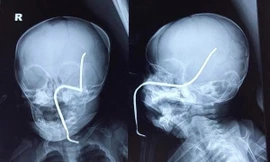

TPO - Bé Nguyễn T.H (8 tháng tuổi ở thị xã Sơn Tây, Hà Nội) bị chiếc máy đang cắt cỏ cách đó khoảng 15m làm bắn văng thanh sắt rỉ nằm ẩn dưới cỏ vào má trái, xuyên thủng hộp sọ.